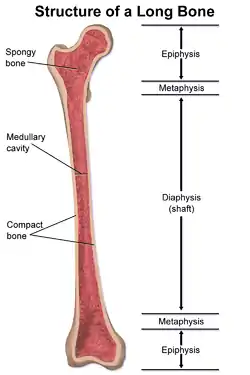

A femoral fracture is a bone fracture that involves the femur. They are typically sustained in high-impact trauma, such as car crashes, due to the large amount of force needed to break the bone. Fractures of the diaphysis, or middle of the femur, are managed differently from those at the head, neck, and trochanter; those are conventionally called hip fractures (because they involve the hip joint region). Thus, mentions of femoral fracture in medicine usually refer implicitly to femoral fractures at the shaft or distally.

Intramedullary nailing

For femoral shaft fractures, reduction and intramedullary nailing is currently recommended.[14] The bone is re-aligned, then a metal rod is placed into the femoral bone marrow, and secured with nails at either end. This method offers less exposure, a 98–99% union rate, lower infection rates (1–2%) and less muscular scarring.[14][15][17]